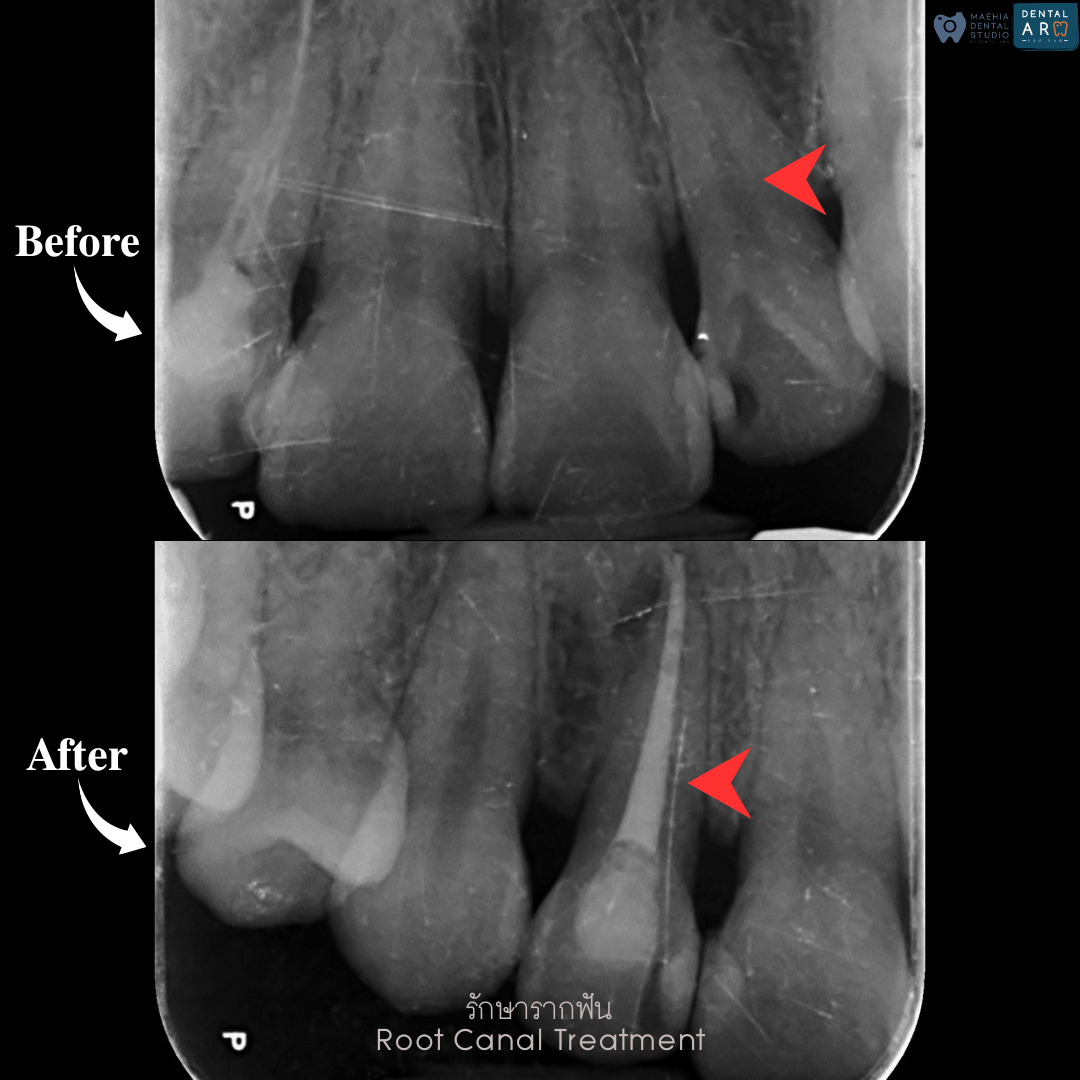

รักษารากฟัน

คือ การรักษาฟันที่เกิดการอักเสบและติดเชื้อภายในโพรงประสาทฟัน และเนื้อเยื่อรอบปลายรากฟัน อันมีสาเหตุมาการอักเสบและติดเชื้อภายในรากฟัน โดยทันตแพทย์จะทำการทำความสะอาดและใส่ยาในคลองรากฟัน และทำการอุดรากฟันเป็นขั้นตอนสุดท้าย การรักษารากฟันจะช่วยเก็บรักษาฟันให้สามารถคงอยู่ในช่องปากต่อได้ โดยไม่ต้องถอนฟันและไม่ต้องใส่ฟันทดแทน